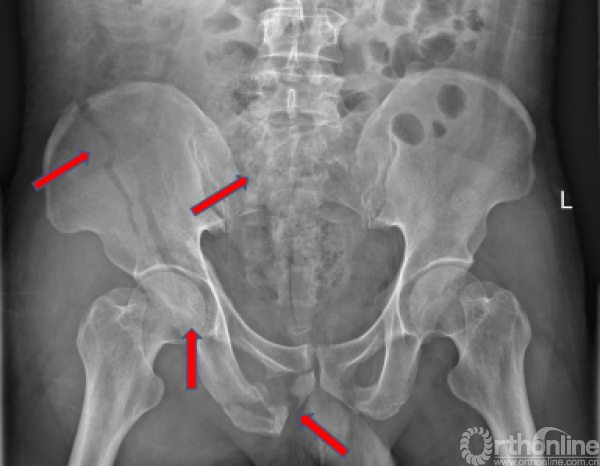

术前X线(2017.09.17)

骨盆正位、骨盆入口位、骨盆出口位

骨折的正确分型

骨盆AO和Tile分型,以及基于骨折的受伤机制和稳定性Young and Burgess分型:APC LC(lc-II型)、VS、CM;髋臼两类十型(前柱合并前壁);骶骨骨折Dennis分型(II区)

骨折移位方向的准确判断(五种+混合)

基本类型:上移、外翻、内翻、旋前、旋后;以及混合型